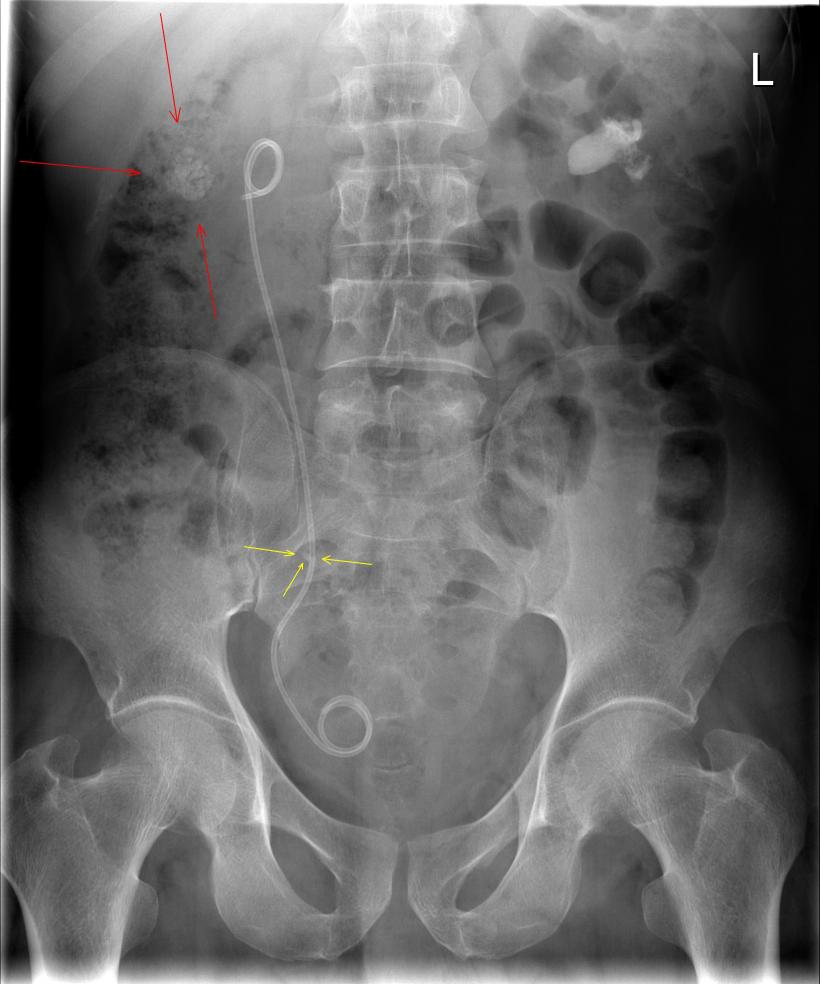

rara, wat is dit

rara, wat is dit